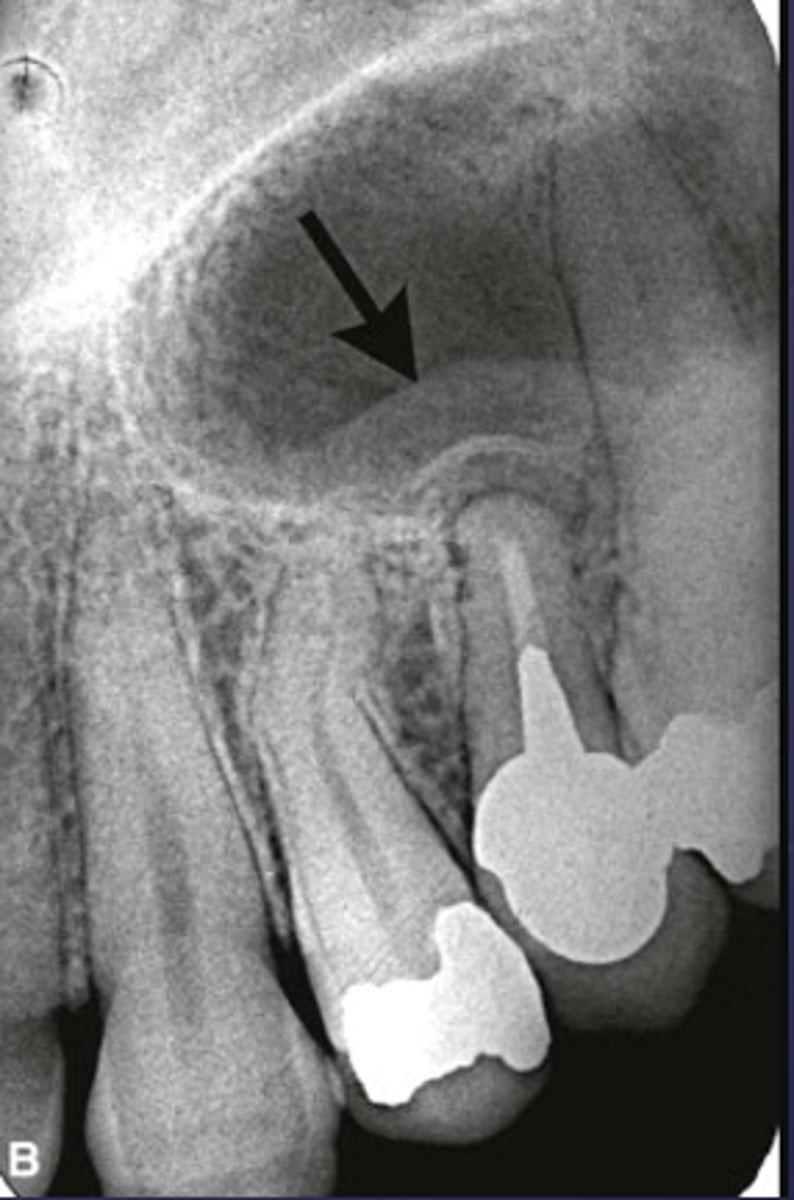

What is the black arrow pointing at?

sequestrae

What is the white arrow pointing at?

periosteal reaction

periosteal reaction (increased bone density)

sequestra

What phase of osteomyelitis does this show?

acute (multiple sequestrae)